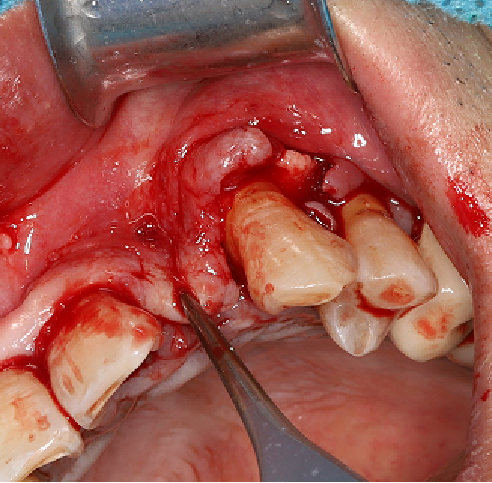

采用不切开骨膜的软组织扩张术——Soft Tissue Extend释放软组织张力

记录翻瓣后原始软组织瓣长度,使用软组织搔刮器(Soft Tissue Extender)冠根向搔刮软组织瓣。

在不切断骨膜的前提下,使用软组织刮治器反复搔刮软组织瓣,可以起到延长软组织瓣的作用。

使用软组织搔刮扩张前后对比:可见在不切断骨膜的前提下,使用软组织搔刮即可获得软组织瓣延长8-9mm。